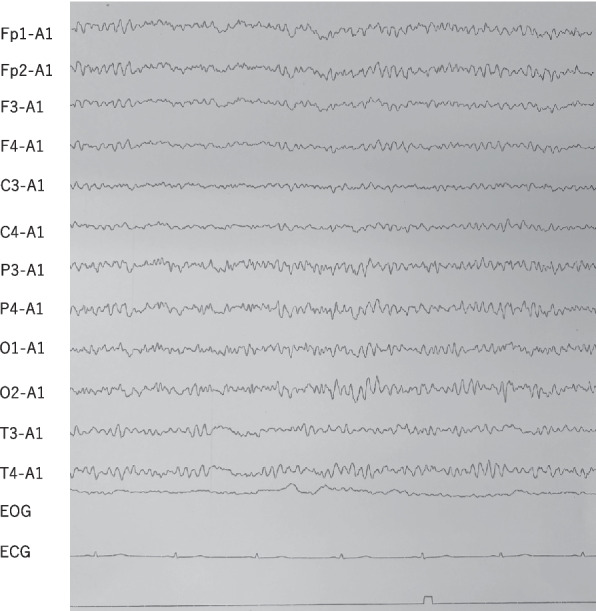

Case presentation: We report five cases of catatonia (including malignant catatonia) associated with schizophrenia or schizoaffective disorder. These cases were treated either in a psychiatric hospital or an outpatient clinic, both of which lacked access to ECT. Extended-release formulation of guanfacine was administered alongside temporary benzodiazepine use, and treatment outcomes were observed. All five patients were in syndromal remission from catatonia following treatment that included guanfacine in combination with other pharmacological interventions. Mild to moderate side effects were observed. These included dizziness and fatigue in one patient, and hypotension and bradycardia in two others. All adverse effects resolved with dose reduction. Complications of catatonia included impaired oral intake requiring nutritional support in two patients and urinary catheterization due to immobility in two patients.